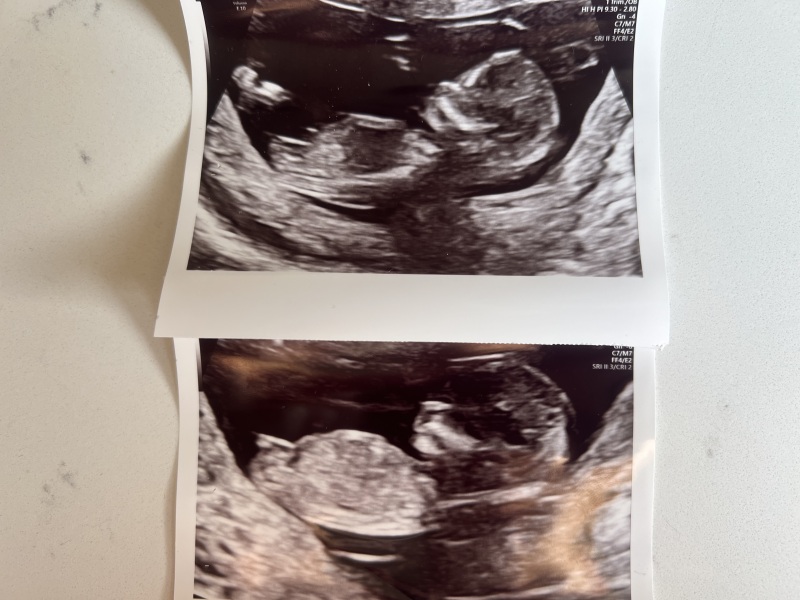

what is your guys thoughts on nub theory with this scan pic? I never found out with my little girl and going to find out the gender this time but i feel so impatient and thought id give this a go for a little fun. I’m 12w 3days.

what do we think 🩵 or 🩷

Nub theory

Clear girl nub 🥰

I think it’s a boy